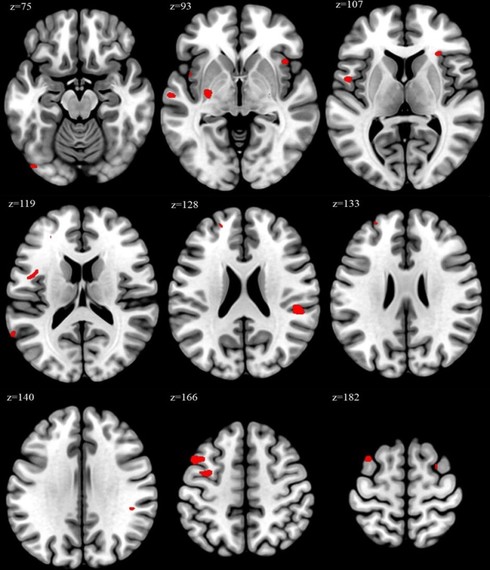

この研究では、医療従事者110人(医師28人、看護師36人、その他の医療従事者46人)に参加してもらった。実験では週52時間以上働く「過労グループ」32人と、週52時間未満の「非過労グループ」78人に分け、脳のMRI検査を実施した。脳容積の差異はVBM(Voxel-Based Morphometry)と「アトラスベース解析」と呼ばれる方法を用いて評価した。

脳の構造を詳細に分析した結果、過労グループでは主に思考や計画立案、意思決定などの「実行機能」と、感情のコントロールに関わる脳領域の容積が増加していることが明らかになった。

具体的には、 アトラスベース解析では左尾側中前頭回という脳領域の容積が過労グループでは非過労グループより19%も大きかった。また、VBM解析では、中前頭回や島皮質、上側頭回を含む17の領域でピーク増加を観察できた。相関分析は、週労働時間と中前頭回、島皮質における脳容積変化の間に正の相関を示した。

研究チームはさらに、喫煙や飲酒、運動などの生活習慣要因を調整した感度分析も行った。その結果、左中前頭回と左ローランド弁蓋、左島皮質、左上前頭回における労働時間とVBMピーク値の関連は、これらの要因を調整した後も有意であった。このことは、観察できた脳構造変化が生活習慣要因だけでは完全に説明できないことを示している。